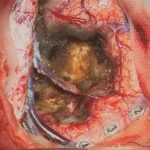

No.’22_42 手術前1

No.’22_42 手術前2

No.’22_42 摘出 前

No.’22_42  摘出 中

No.’22_42 摘出 後